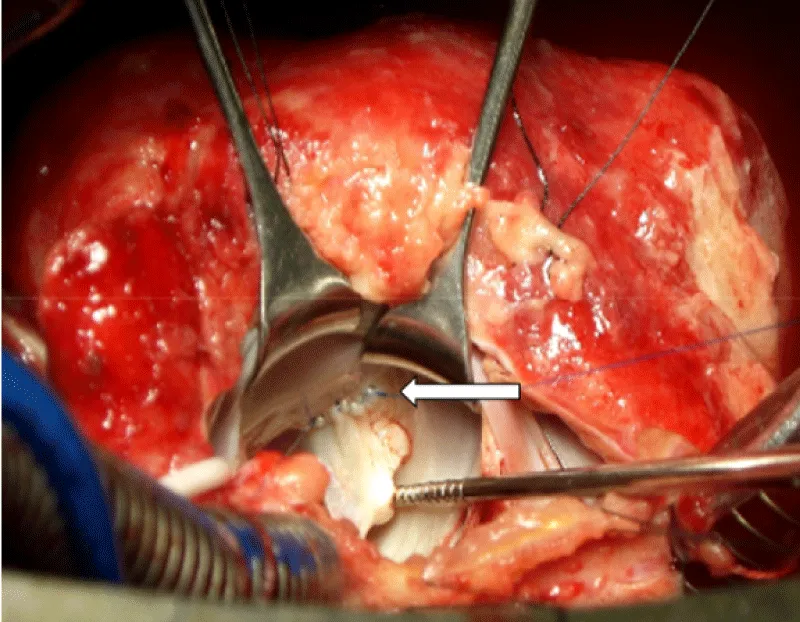

After sternotomy and opening of the pericardium which was thickened, an effusion with false membranes is revealed. There was no obvious bleeding point, and the point of break-in could not be objectified. After initiation of routine cardiopulmonary bypass, aortic cross-clamping and adequate myocardial protection, the mitral valve was exposed through a trans-septal approach, we revealed a 2 cm perforation in the anterior mitral valve (Figure 2). After suturing the defect (Figure 3), we proceeded to posterior mitral ring reduction by suture annuloplasty.

Figure 2: Perforation of the body of the anterrior mitral valve (white arrow).